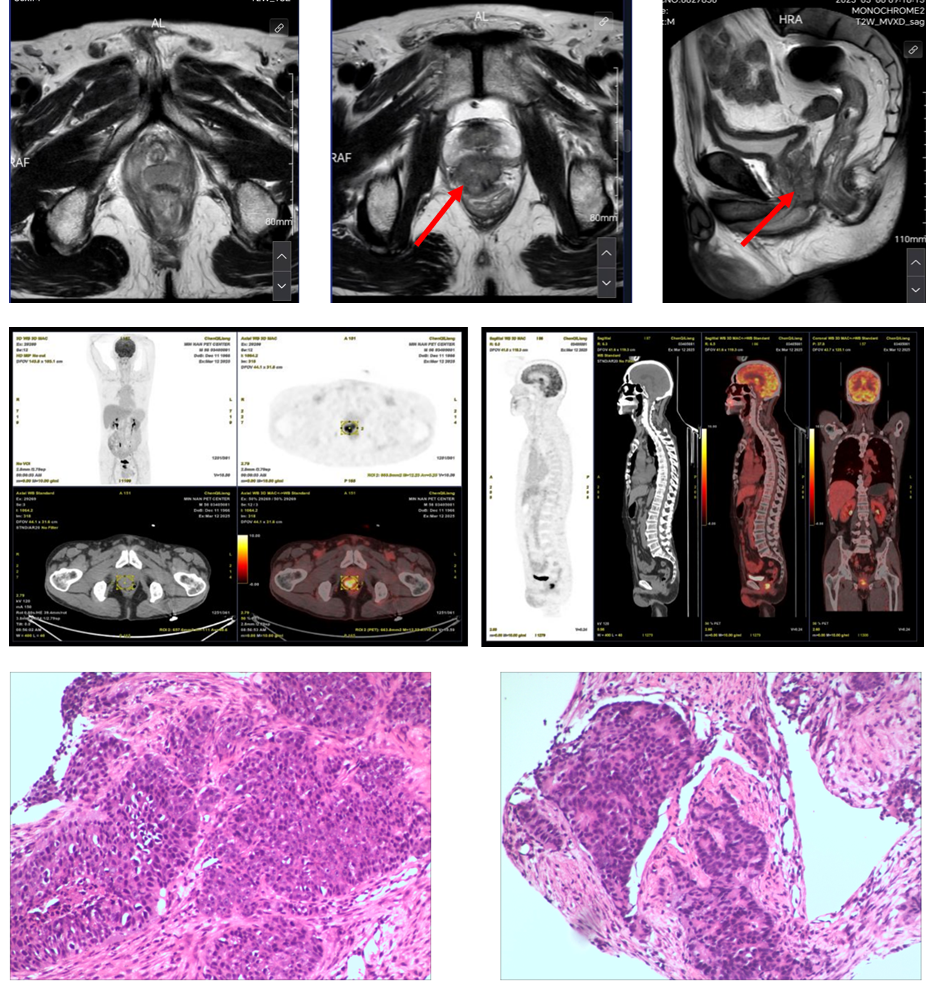

本例患者男,58 岁,有糖尿病病史,血糖控制尚可,无明确前列腺癌家族史。2025年3月因“进行性排尿困难1年”就诊当地医院,入院后查肿瘤标记物发现PSA 0.96ng/ml。直肠指检提示前列腺明显增大、质地偏硬、表面可触及多个结节。MRI扫描显示前列腺大小约4*4.4*3.8cm,外周带多发团块状异常信号,累及直肠,PI-RADS评分5分。PET-CT检查显示前列腺右叶外周带高代谢结节,考虑肿瘤性病变侵及直肠可能,盆腔多发稍大淋巴结,转移待排。经前列腺穿刺活检证实为前列腺腺泡腺癌,Gleason评分5+4=9分(ISUP 5级)(图2)。综合临床及影像学资料,诊断为前列腺癌,cT4N1M0(IV期)。基因检测提示BRCA2及其相关通路存在多基因致病性改变,提示同源重组修复(HRR)功能受损,符合PARP抑制剂潜在获益的分子亚型。结合本例cT4N1M0的局部肿瘤负荷较高及BRCA2/HRR缺陷这一高风险生物学特征,可推测其疾病进展与复发/转移风险相对更高。鉴于患者仍处于可手术窗口期,拟采用以PARP抑制剂为核心、联合雄激素受体(androgen receptor,AR)通路深度抑制的精准新辅助强化策略,以期获得更深层次的肿瘤学缓解、降低潜在微小残留负担,并优化后续根治性切除的局部条件与病理学结局。在此依据下,患者符合SEGNO研究BRCA1/2突变队列的入组标准,经多学科团队(multidisciplinary team,MDT)讨论后纳入该队列并启动新辅助三联治疗方案。

根据SEGNO研究预设方案,患者接受NHA + ADT + PARP抑制剂的新辅助三联治疗,具体用药为:瑞维鲁胺 240 mg 口服 每日一次+戈舍瑞林缓释微球 3.6 mg 肌内注射,每 4 周一次+帕米帕利 60 mg 口服 每日两次。整个新辅助治疗历时约6个月,期间患者总体耐受性良好,未出现剂量限制性毒性。随访过程中PSA水平迅速下降并维持在不可测水平(图3);新辅助治疗结束时复查PSMA PET/CT未见前列腺原发灶、盆腔淋巴结及远处骨骼异常摄取灶,与基线相比病灶代谢信号基本消失,影像学评估达到临床完全缓解(cCR)(图4)。

新辅助治疗结束并经术前评估确认具备手术条件后,患者接受机器人辅助根治性前列腺切除术联合盆腔淋巴结清扫。术中未观察到显著治疗相关纤维化黏连或广泛肿瘤浸润,手术顺利完成,术后恢复平稳。术后病理检查显示前列腺标本内仅残留极少量散在癌细胞,瘤床肿瘤细胞减少>90%,肿瘤负荷较基线显著下降,切缘阴性,盆腔淋巴结未见癌转移,病理学评估显示达到病理最小残留病灶(pMRD),并接近病理完全缓解(pCR)。综合术前cT4N1M0分期、BRCA2/HRR通路致病性改变这一高风险生物学背景及新辅助后PSMA PET/CT评估为cCR的结果,本例呈现影像学与病理学一致的深度缓解(pMRD,近pCR)。该个案提示在BRCA2/HRR缺陷亚组中,PARP抑制剂参与的分层三联新辅助策略可获得早期深度肿瘤学缓解,并可能预示更有利的长期结局,尚需进一步随访数据加以验证。同时,本病例亦为SEGNO研究所采用的基因分层新辅助治疗路径提供了临床层面的支持性证据。